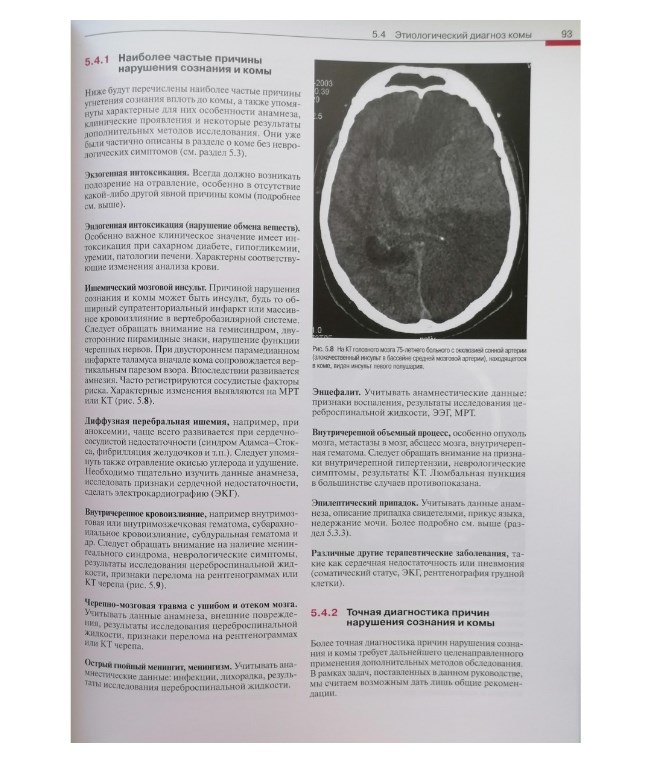

:background_color(FFFFFF):format(jpeg)/images/article/motor-cortex/XiebAmFl6VnmTW8eAak5Ww_thumbnail_T990_corticospinal_and_corticobulbar_tracts_PK.png)

Раздел: Вселенная идей